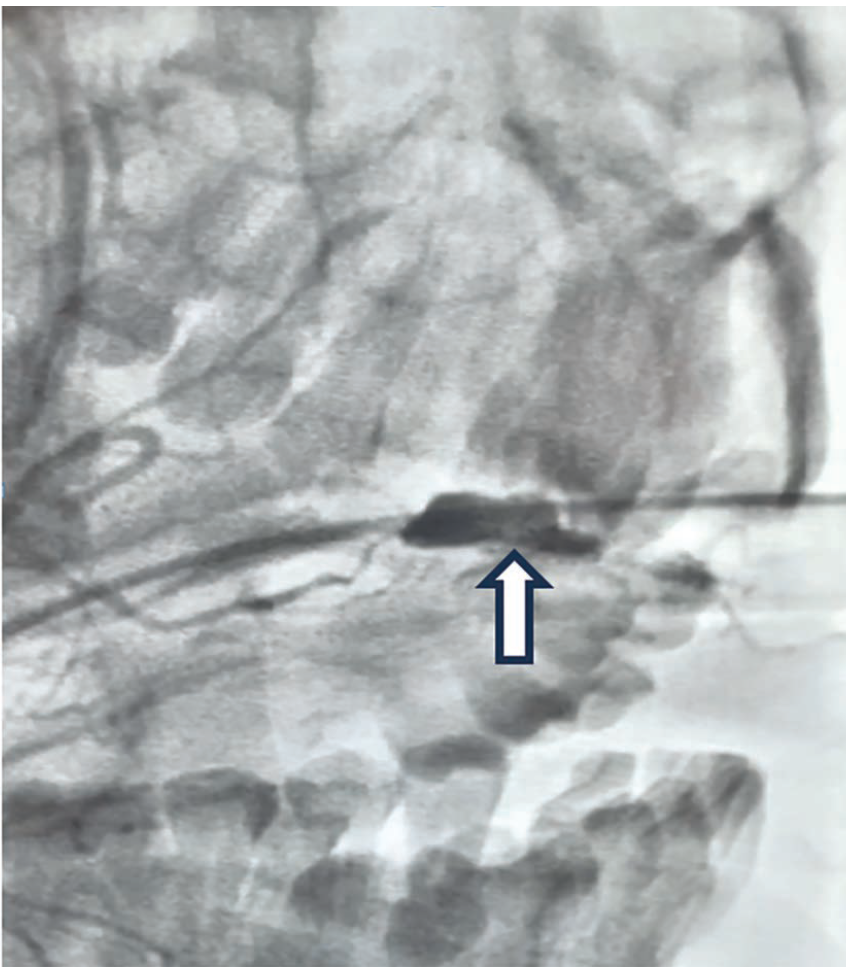

Baseline angiography demonstrated major bleeding from the main branch of the facial artery prior to bifurcation (Figure 2).